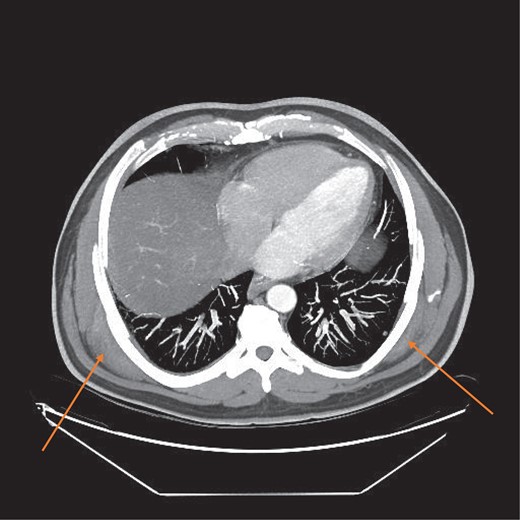

MRI confirmed the diagnosis and showed a second lesion on his left side, also at the infrascapular area (Figs 1–3). The patient had not complained of any symptoms to his left side or his left shoulder joint. After an extensive discussion with the patient and his family, we decided on a computerized tomography (CT) guided true cut biopsy to confirm the diagnosis (Fig. 4).

The tissue sample was inadequate for diagnosis and at this stage the patient decided to proceed with surgery in the form of an excision biopsy rather than a repeat CT guided biopsy. We decided to excise the symptomatic lesion on the right side first and then reevaluate the left side post-operatively. The left sided lesion remained asymptomatic and clinically impalpable.